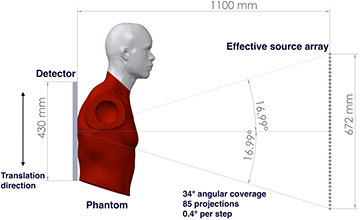

Standard image High-resolution imageThe system geometry is shown in figure 3. The source-to-detector distance is 110 cm, with the source array aligned to the centerline of the detector. The 75 focal spots with 4 mm pitch, in the present x-ray source array, cover a 15.7° angular span relative to the detector center. Translation of the detector and the phantom together, relative to the source array, allows extended acquisition geometries with variable source-to-detector distances, angular coverage, and number of projection views. Due to limitations of the optical table size, the maximum effective source array length that can be emulated is 672 mm. However, the resulting 34° angular coverage relative to the detector center is comparable to current commercial systems. This effective source array has a source-to-source pitch of 4 mm and can generate up to 169 projection views. By choosing different combinations of sources, one can simulate various imaging configurations with different numbers of projections, angular span, and source-to-source pitch. For most images acquired in this study, we used every other source in this effective source array. This produced up to 85 projections with 0.4° angular steps between projections, which is comparable to commercial DCT systems.

Figure 3. An illustration of the imaging geometry in the bench top stationary chest tomosynthesis system. The source-to-detector distance is 110 cm. By moving the detector and phantom together, parallel to the source array, we are able to emulate different imaging geometries. In the current bench-top proof-of-concept setup, the effective x-ray source array is able to cover up to a 34° angular span relative to the detector center with up to 85 projections.